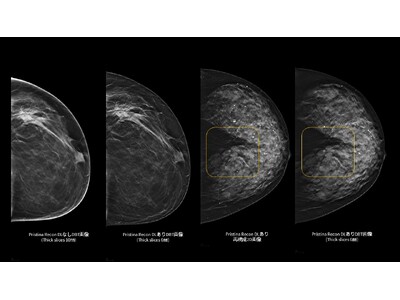

「Pristina Recon DL」は、ディープラーニングと逐次近似再構成技術を活用した、デジタルブレストトモシンセシス(DBT/3Dマンモグラフィ)向けの画像再構成技術です。また、被ばく線量を増加させることなく、高画質で安定したDBT/3Dマンモグラフィ画像の提供を目指します。

さらに、ディープラーニングを用いた高度な画像再構成技術により、アーチファクト(虚像)や視覚的ノイズを低減し、微細構造の視認性を向上させます。これにより、DBT/3Dマンモグラフィおよび再構成2D画像の双方において、読影に必要な情報をより明確に可視化し、診断を支援する読影環境の向上に貢献します。